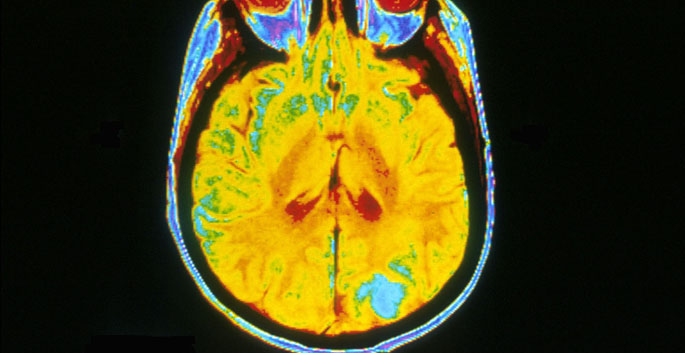

Treatment with a drug used to prevent organ rejection partially reverses the course of tuberous sclerosis, research in mice suggests.